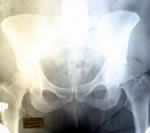

Обследование

по поводу отдаленных метастазов |

|